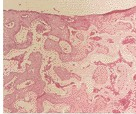

髂骨活检的组织形态学分析仍然是诊断肾性骨营养不良(ROD)的金标准,ROD包括由慢性肾脏疾病(CKD)引起的各种组织学病变。本文主要目的是评估ROD背景下与骨组织形态计量学相关的各种问题,针对骨活检程序、样本处理、阅读和报告发现达成共识。 展开